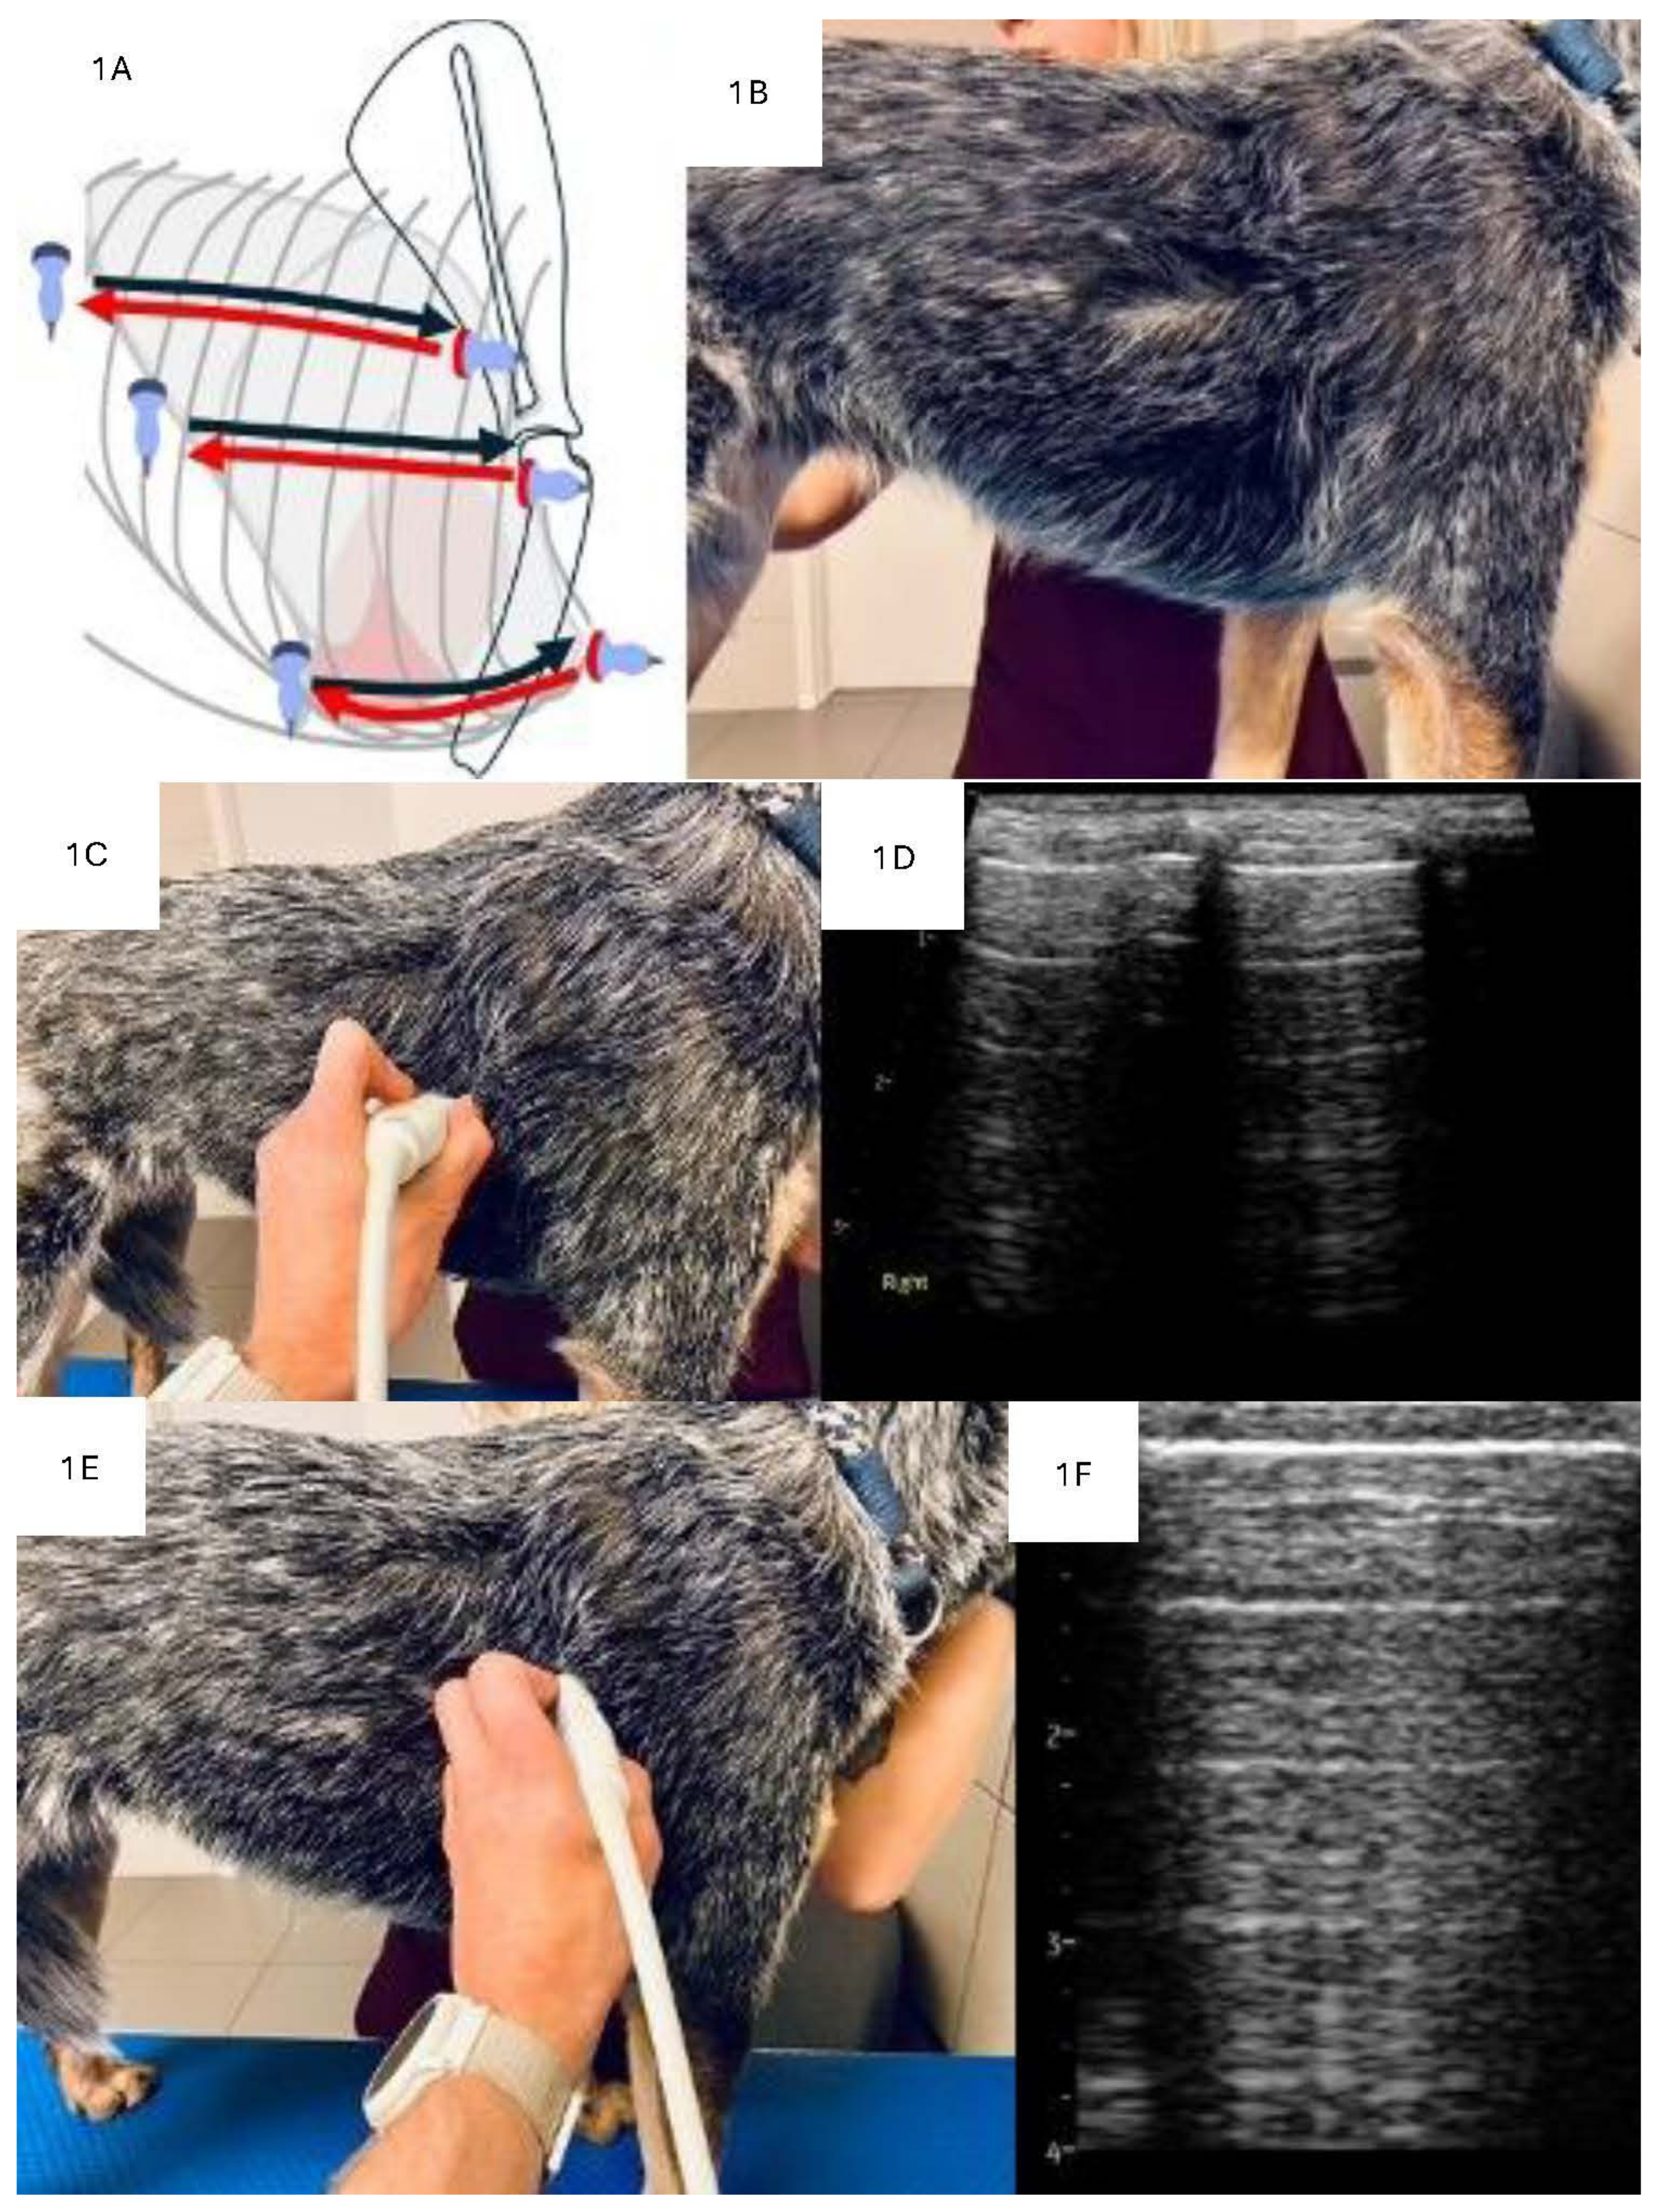

2.3. LUS Examination Technique

2.4. Analysis of Consolidations in 2D